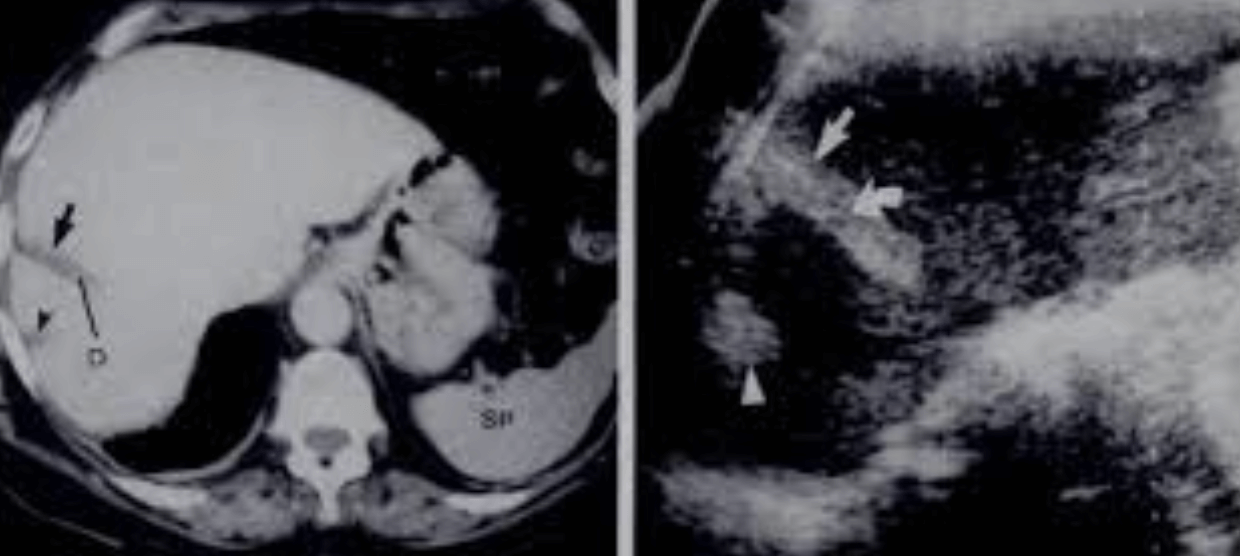

2. Long left lobe of the liver = Beaver tail liver

Beaver tail liver 좌엽이 길고 커져서 비장에 인접해 있다. 마치 비장의 피막하 혈종(subcapsular hematoma)처럼 보인다. 주로 마른 여자에서 확인된다.